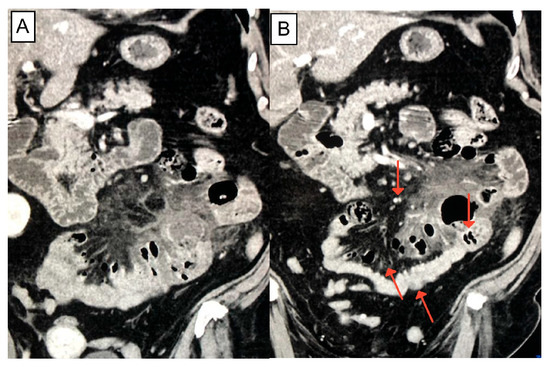

2. Case Presentation